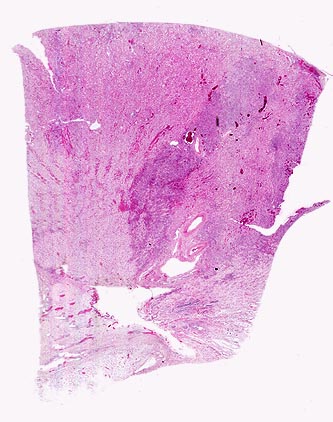

PathoPic – image database / PathoPic ID 4988 - akute Pyelonephritis (destruktive interstititelle Nephritis)

akute Pyelonephritis (destruktive interstititelle Nephritis)

Entzündung infektiös

Niere

Niere, Harnwege

Zusatzbefund

Uretero- und Nephrolithiasis

Fieber mit Schüttelfrost, Übelkeit und Flankenschmerzen. Dysurie. Nachweis von E. coli in der Urinkultur und in Blutkulturen. Exsiccose.

Histologie

Scan